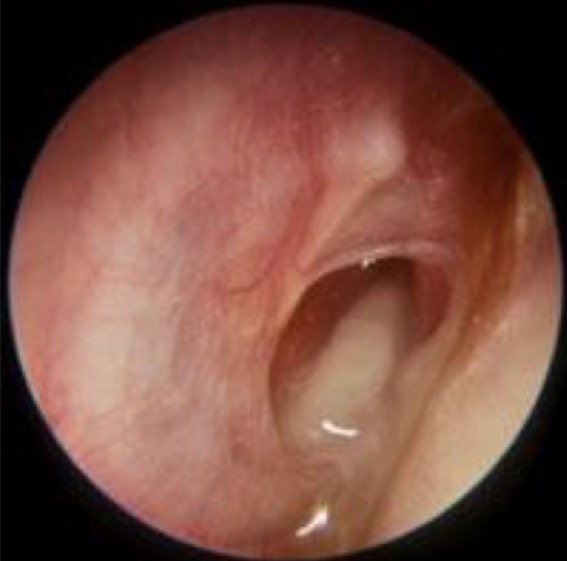

Comment on this tympanic membrane

Fluid behind tympanic membrane

No malleus handle

No cone of light

Not translucent